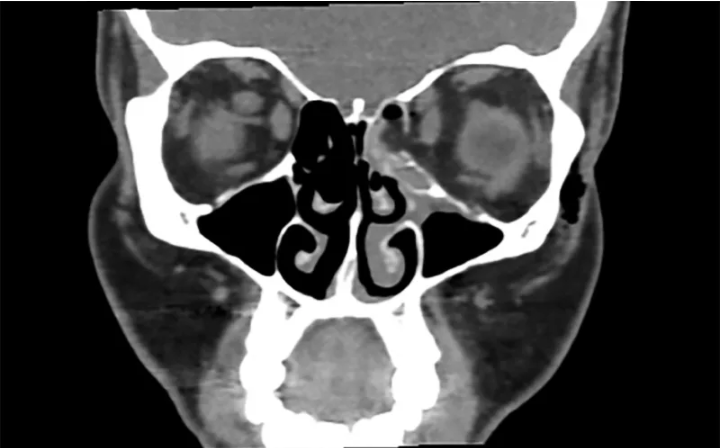

En el hospital fue sometida a una tomografía que mostró una fractura en el ojo izquierdo. También mostró que el hueso que rodeaba el ojo se había roto.